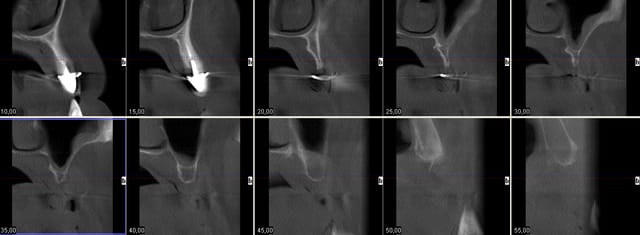

Je rentre cette apm et je tente de charger ton examen cone beam

Cas promis... à dentiste 57 et à growler... le voici

Pour Pluton aussi ;-))))

Bon je cesse la liste sinon je vais créer un ordre de préséance entre vous , ordre malvenu sans doute ;-)))

Pp